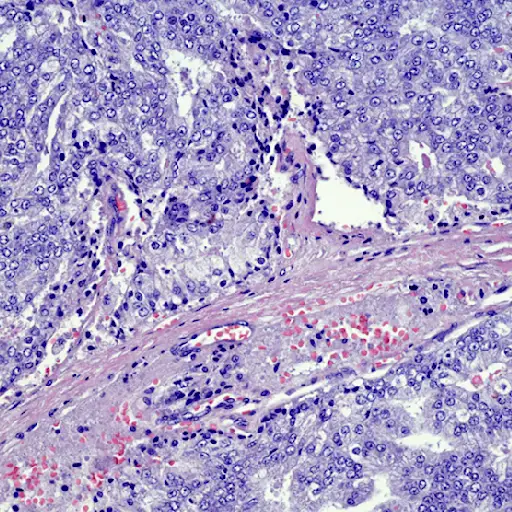

男人也有乳管

华盛顿特区乔治·华盛顿癌症中心乳腺癌项目主任、医学博士瑞秋·布莱姆说,男性最常见的乳腺癌是导管癌,形成于乳管

在男性中少见的是始于产奶腺体的小叶癌(男性很少有),以及以红肿外观为特征的炎症性乳腺癌。